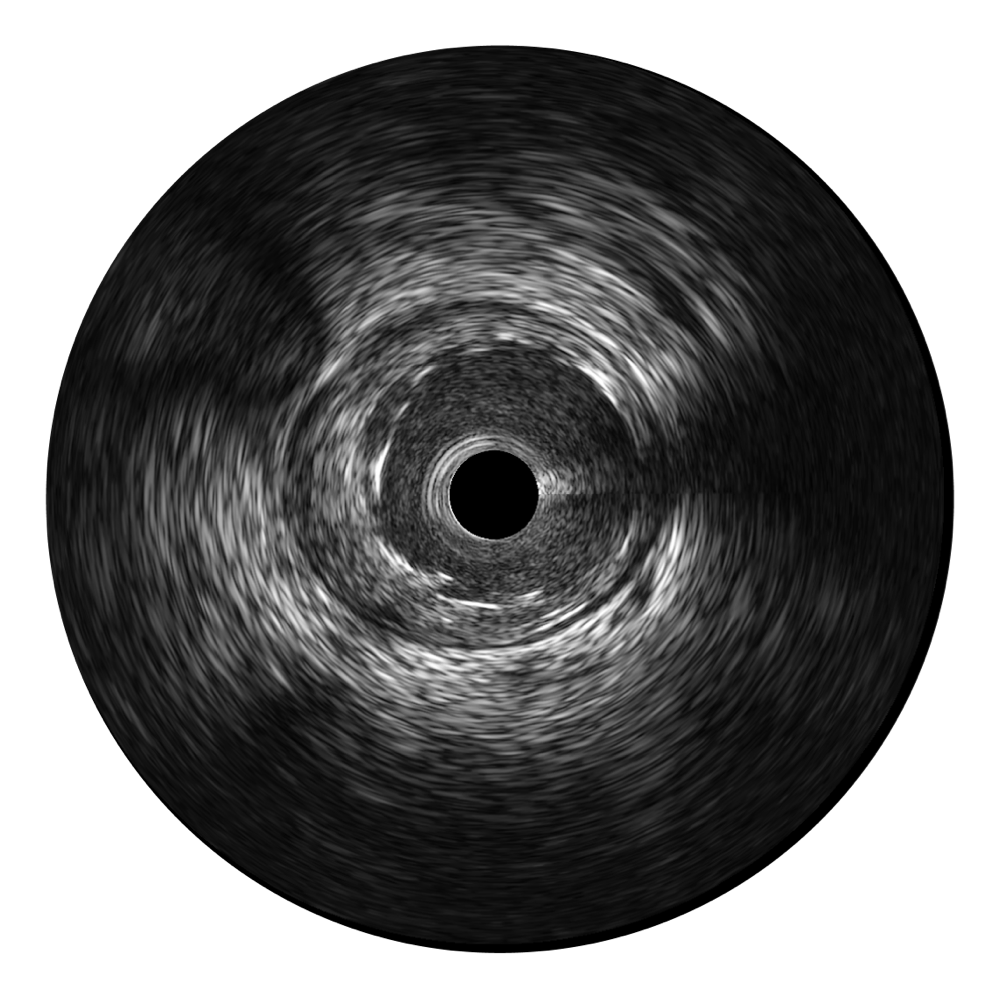

传统IVUS图像

对比传统IVUS导管成像,新葡的京集团8814检测站宽频IVUS图像的近场支架梁显影更细腻,远场中膜外血管仍清晰可辨,兼顾远中近,兼顾分辨力与穿透深度